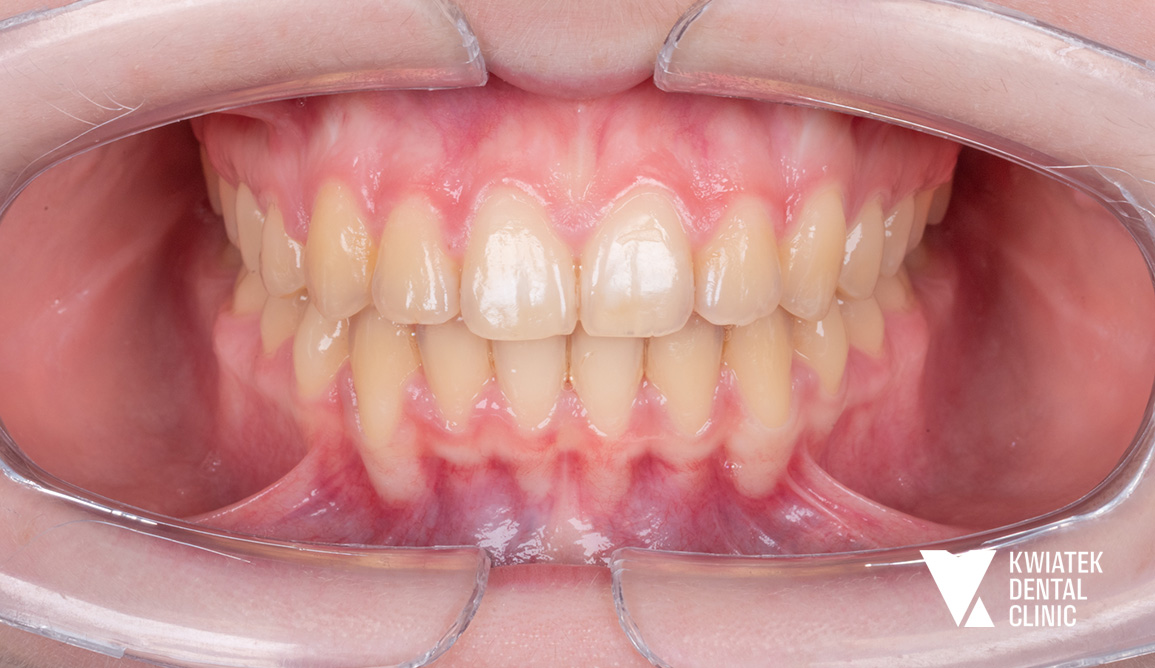

Luksus dyskretnej ortodoncji oparty na zaawansowanej technologii nakładkowej

Pacjentka zgłosiła się do kliniki z potrzebą kompleksowej poprawy zarówno funkcji zgryzu, jak i estetyki uśmiechu. W badaniu stwierdzono zgryz krzyżowy, stłoczenia zębów oraz liczne problemy wymagające leczenia zachowawczego i protetycznego, co wymagało wieloetapowego, interdyscyplinarnego podejścia. Terapię poprzedziło staranne przygotowanie jamy ustnej obejmujące ekstrakcję zębów mądrości, profesjonalną higienizację oraz odbudowę osłabionych struktur. Następnie wdrożono zaawansowane leczenie ortodontyczne z wykorzystaniem nowoczesnego systemu nakładkowego. Rezultatem jest harmonijny, stabilny zgryz, idealnie ukształtowane łuki zębowe oraz wyraźnie odmłodzony, jasny uśmiech, podkreślony profesjonalnym wybielaniem.